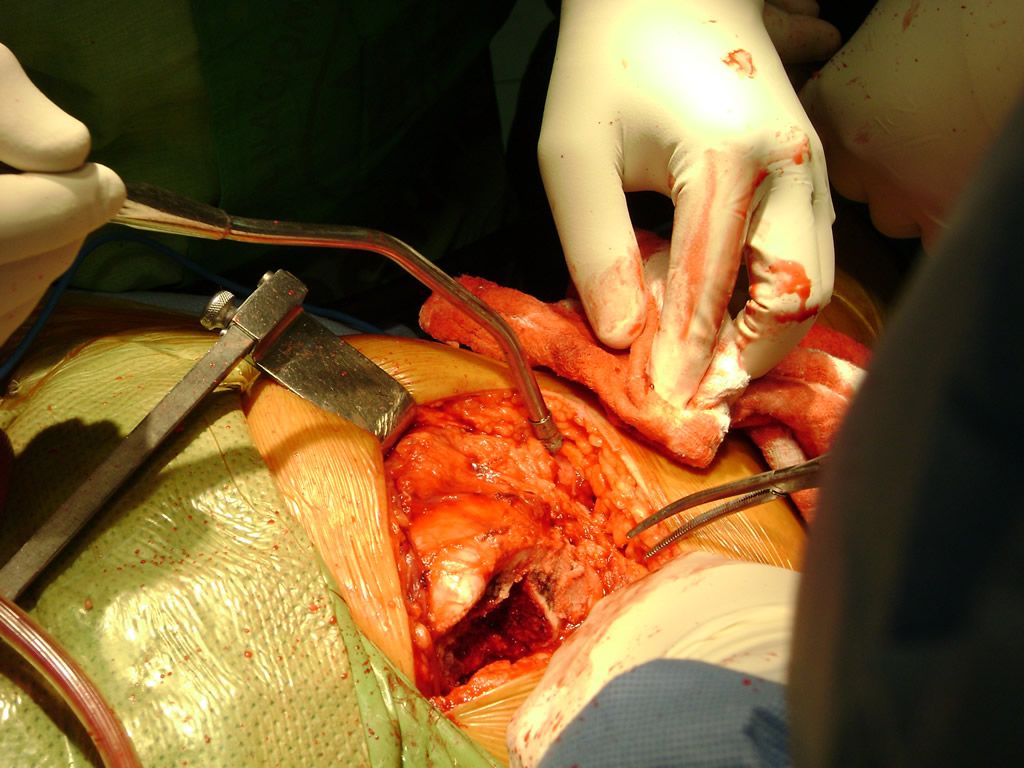

Aunque cada uno de estos huesos puede fracturarse por separado, normalmente la rotura es una lesión que se produce de forma conjunta

La mayor parte de las roturas implican a la parte proximal del hueso (parte del hueso próximo a la rodilla) o a la parte distal (parte del hueso cerca del tobillo).

Debido a la fina cobertura de piel que recubre la tibia y el peroné, las fracturas generalmente son abiertas, es decir, el hueso roto rasga la piel, atravesándola. Las fracturas de tibia y peroné generalmente se producen por un fuerte impacto o torsión.